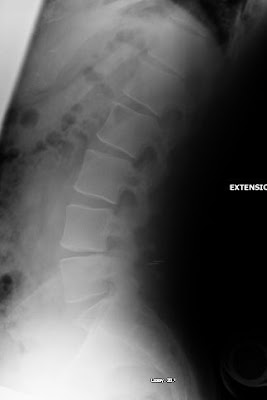

Here are the X-rays:-

(Hyper Extension X-Ray courtesy of BCH)